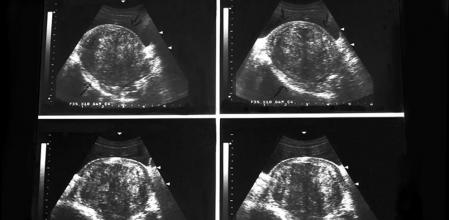

Los miomas o fibromas uterinos salen a la luz gracias a revisiones rutinarias en las que el médico detecta alguna anomalía. Una vez existe la sospecha, el médico ordena la realización de una ecografía y de análisis de laboratorio. Solo cuando hay dudas se recurre a una resonancia magnética.